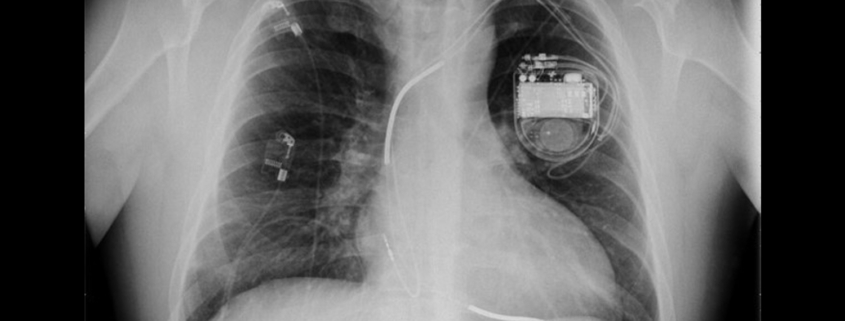

Elektrostimulator srca (engl. pacemaker) je električni uređaj koji se ugrađuje ispod kože pacijenta kako bi održavao ili povratio normalan srčani ritam.

Srčana resinkronizacijska terapija (engl. Cardiac resynchronization therapy – CRT) je zahvat kojim se liječe neke vrste srčanog zatajivanja. Srčano zatajivanje je stanje kada srce ne istiskuje („punpa“) dovoljno krvi.

Ugradbeni kardioverter defibrilator (engl. implantable cardioverter defibrilator – ICD) je elektronički uređaj sličan elektrostimulatoru srca koji se ugrađuje ispod kože pacijenta.